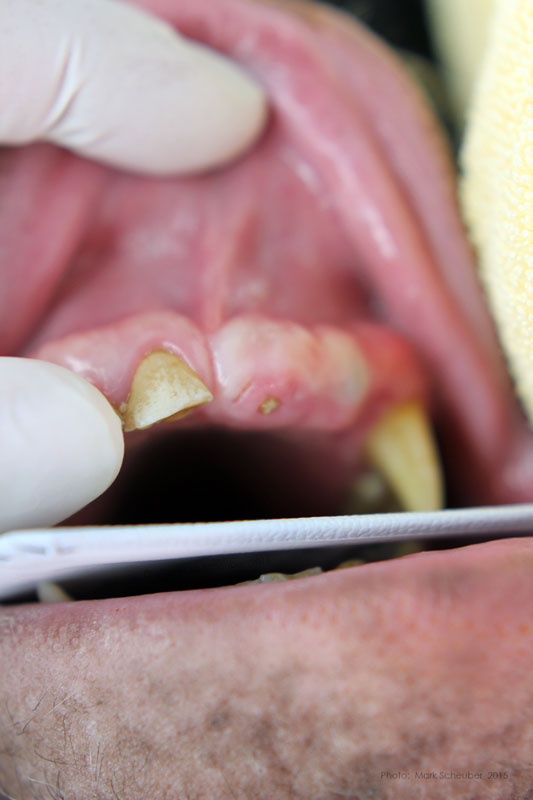

Extracted roots.

Roots

Simple interrupted sutures placed with knots inside the wound so that Makanza will find it difficult to disturb them with his fingers and tongue.Rachel - Mongolian (Bactrian) Camel